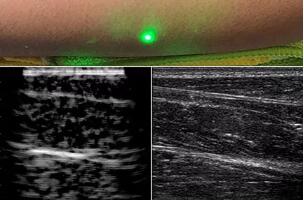

臨床應(yīng)用的無(wú)創(chuàng)超聲,要求探頭與人體皮膚直接接觸來(lái)向身體傳導(dǎo)高頻振動(dòng)的超聲波。但是,有一些特定的患者卻在超聲檢查時(shí)受到限制,比如兒童、燒傷患者和敏感皮膚患者等。而近日麻省理工學(xué)院的研究人員證明,確實(shí)有可能使用激光在不接觸皮膚的前提下對(duì)患者進(jìn)行超聲波掃描。

而麻省理工學(xué)院的研究小組現(xiàn)在開(kāi)發(fā)了一種使用激光檢測(cè)皮膚上超聲波振動(dòng)的方法,以便可以使用一種激光使皮膚產(chǎn)生共振,而另一種則可以檢測(cè)到振動(dòng),從而達(dá)到“遠(yuǎn)程超聲掃描”的作用。

目前,研究人員已經(jīng)與健康的志愿者測(cè)試了他們的系統(tǒng):從半米遠(yuǎn)處掃描了他們的前臂,并將這些結(jié)果與傳統(tǒng)超聲的結(jié)果進(jìn)行了比較。他們能夠觀察到深達(dá)6厘米的組織,并能看到肌肉,脂肪和骨頭,并報(bào)告其結(jié)果可與標(biāo)準(zhǔn)超聲相媲美。

研究人員用一種激光裝置測(cè)試了這個(gè)想法,該裝置使用一個(gè)波長(zhǎng)為1,550納米的脈沖激光來(lái)產(chǎn)生聲波,并使用第二個(gè)連續(xù)激光,調(diào)諧到相同的波長(zhǎng)以遠(yuǎn)程檢測(cè)反射的聲波。第二個(gè)激光器是靈敏的運(yùn)動(dòng)檢測(cè)器,可測(cè)量聲波從肌肉,脂肪和其他組織反射回來(lái)而引起的皮膚表面振動(dòng)。反射的聲波產(chǎn)生的皮膚表面運(yùn)動(dòng)會(huì)導(dǎo)致激光頻率發(fā)生變化,這種變化可以測(cè)量。通過(guò)機(jī)械掃描人體上的激光,科學(xué)家可以獲取不同位置的數(shù)據(jù)并生成該區(qū)域的圖像。